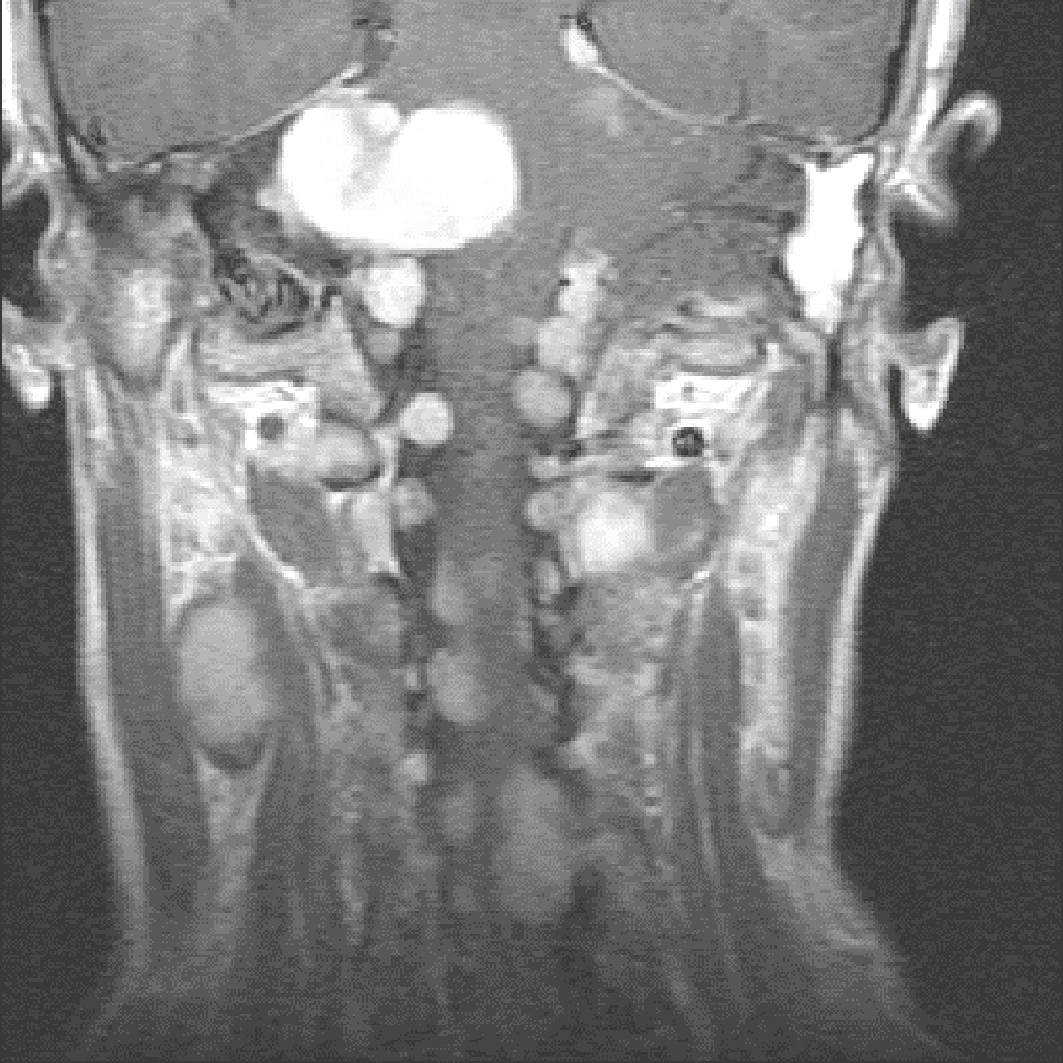

Fig. 7.8

Schwannome « en sablier » thoracique T5-T6 gauche.

Lésion extramédullaire extradurale, bien limitée, en forme de sablier, développée dans le foramen intervertébral T5-T6 gauche et étendue en dehors dans les espaces paravertébraux et en dedans dans le canal rachidien avec léger effet de masse sur la moelle. Le foramen est très élargi, témoignant du développement lent de la lésion. La lésion est en hyposignal T1, en hypersignal T2 et est rehaussée de manière homogène après injection. A. T1 axial. B. T1 axial après injection. C. T1 frontal après injection. D. T1 sagittal après injection.Les coupes axiales T1 et T2 (A et B) montrent une masse bien circonscrite s’étendant depuis le foramen intervertébral gauche en T5-T6. Elle présente un hyposignal modéré en T1 (A) et un hypersignal franc en T2 (B), sans signe de nécrose. L’image coronale (C) met en évidence la configuration en sablier, avec une extension intra- et extrarachidienne à travers le foramen, typique d’un schwannome foraminal. Sur la coupe sagittale (D), la masse refoule latéralement la moelle thoracique sans l’envahir, avec un effet de masse net mais sans œdème médullaire associé. Les contours sont réguliers, et l’aspect homogène après injection est en faveur d’une lésion bénigne d’origine nerveuse.

• Ils peuvent survenir dans le cadre d’une neurofibromatose de von Recklinghausen, surtout s’il en existe plusieurs, des signes cutanés (taches café au lait), des antécédents familiaux (fig. 7.9).

Fig. 7.9

Neurofibromes multiples responsables d’une compression médullaire dans le cadre d’une neurofibromatose de type 1 (NF1).

La NF1, ou maladie de von Recklinghausen, est une affection autosomique dominante, à pénétrance clinique complète mais d’expression variable, de manifestation neurocutanée cliniquement hétérogène caractérisée par des taches café au lait, des nodules de Lish, des lentigos sur les aisselles et sur la région inguinale, et de multiples neurofibromes, liée à l’anomalie du gène suppresseur de tumeur NF1 (voir chapitre 26 – item 299).L’image montre une coupe coronale T1 avec injection de gadolinium centrée sur la région cervico-thoracique. On observe une multitude de lésions arrondies, bien circonscrites, réparties le long des nerfs rachidiens bilatéraux, dont certaines présentent un rehaussement intense après contraste. Ces nodules sont compatibles avec des neurofibromes plexiformes multiples. Plusieurs d’entre eux élargissent les foramens intervertébraux, notamment au niveau cervical moyen, avec un refoulement manifeste du contenu rachidien. L’effet de masse exercé sur la moelle cervicale est visible en position centrale, suggérant une compression médullaire d’origine extracanalaire. Ce tableau est typique d’une neurofibromatose de type 1 avec complications neurologiques.